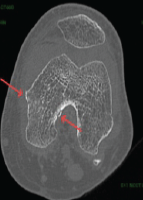

A 12-year-old girl (right hand dominant) presented with a congenital right upper limb isolated non-syndromic radial club hand (unclassified as per Heikel’s or Bayne and Klug classifications). Her main complaint was flexion deformity of the right upper limb at the wrist and elbow joint levels without any functional deficit of the hand. X-ray shows the presence of distal radial epiphysis with a radially deviated integral wrist joint (maintained radio-carpal, ulno-carpal and distal radio-ulnar joints), absence of diaphysis and proximal radius, and shortened ulna with a radial bent (Fig. 1).

Figure 1: Pre-operative pictures (a) the affected right upper limb deformity; (b) skiagram showing the same; (c) pre-operative markings.